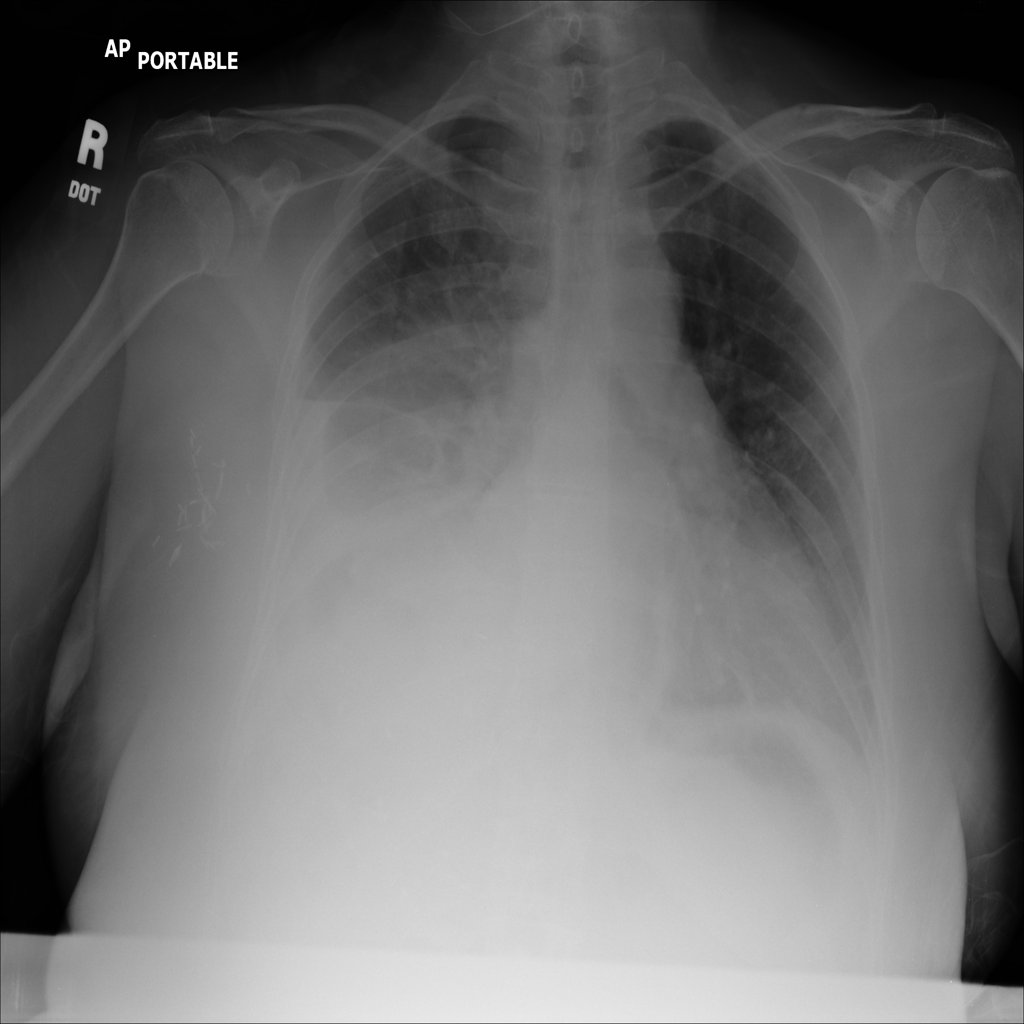

Pleural Effusion

Pleural effusion means extra fluid has collected around the lung in the pleural space. It can happen with heart problems, infection, inflammation, or other underlying conditions.

Showing up to 90 reference images for Effusion.

PAT-86C8 · IMG-000Effusion

PAT-86C8 · IMG-000

PA